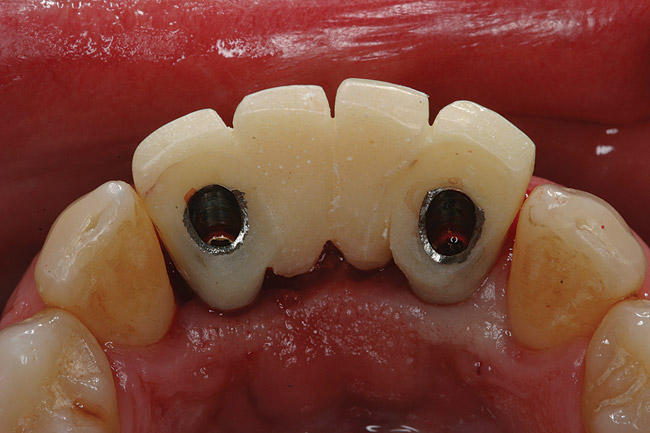

Preoperatively, 1 g of amoxicillin was administered. Using local anesthesia (lidocaine 1:100,000 epinephrine), extractions of teeth No. 23 to No. 26 were performed without raising a flap and with gentle luxation to preserve the remaining facial osseous plate. The sockets were curetted prior to implant placement. A vacuum-formed surgical guide, fabricated based on a diagnostic wax-up of the desired tooth positions for the subsequent fixed prosthesis, was used during implant placement. Osteotomies were performed at sites No. 23 and No. 26 and positioned toward the lingual aspects of the sockets (Figure 3A and Figure 3B). Two tapered implants (OsseoTite™ 313, BIOMET 3i™, Palm Beach Gardens, FL) measuring 3.25 mm x 13 mm were placed. Conical prosthetic abutments (3-mm height) were used to facilitate joining the two implants in a screw-retained fixed partial denture (Figure 4). A laboratory-processed acrylic-resin provisional restoration was altered to allow connection to the temporary cylinders. The provisional was placed into the vacuum-formed surgical guide that was now used to maintain the provisional in the correct 3-dimensional position (Figure 5) while being attached to the temporary cylinders with acrylic resin intraorally. Once a sufficient amount of acrylic resin was placed to secure the cylinders to the provisional, it was removed from the mouth and its contours were completed at the laboratory bench (Figure 6A). The two central incisor sockets were grafted with small-particle allograft material (Puros® Allograft, Zimmer Dental, Carlsbad, CA) to maintain gingival architecture beneath two ovate pontics (Figure 6B). The provisional restoration was inserted and the screws tightened to 20 Nt-cm of torque.

Figure 4  Tapered implants with conical transgingival abutments and temporary cylinders in place.

Figure 4